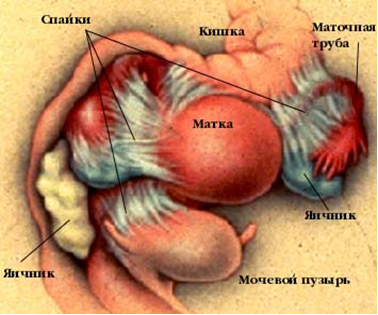

О перитонеальной форме бесплодия говорят в случаях, когда спайки возникают в брюшной полости вокруг маточных труб, между маточными трубами и яичниками, между маткой, придатками, кишечником или другими органами брюшной полости (рис. 2).

Рис. 2. Спайки в малом тазу

В любом из вариантов трубного или перитонеального бесплодия имеется механическое препятствие, не позволяющее сперматозоидам и яйцеклетке попасть в маточную трубу. Проблема осложняется тем, что при воспалении образуются не только спайки, но страдает и сама стенка маточной трубы. Эпителий трубы утрачивает ворсинки, стенка трубы утолщается, становится плотной, теряет эластичность. Это происходит потому, что в результате воспаления мышечная ткань замещается соединительной, т.е. происходит склерозирование тканей: труба теряет свои функциональные способности.